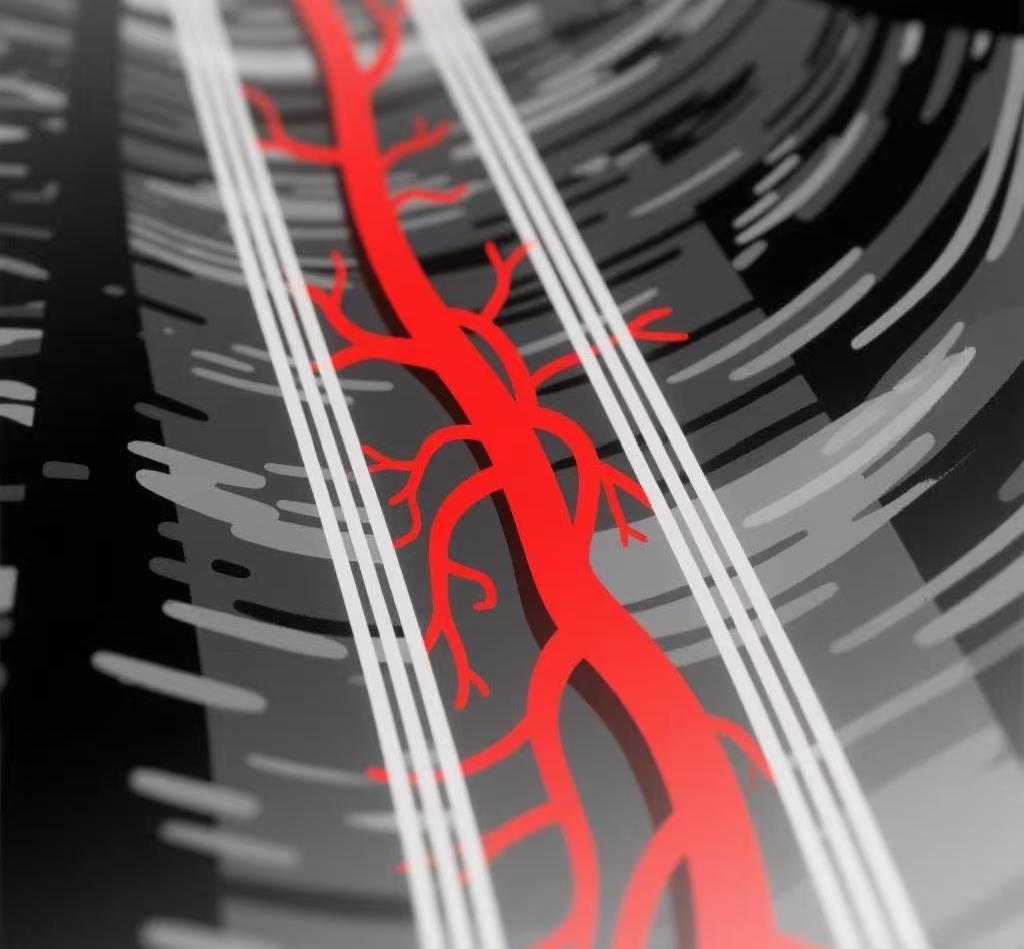

四維超聲技術(shù)清晰呈現(xiàn)器官細(xì)微血流